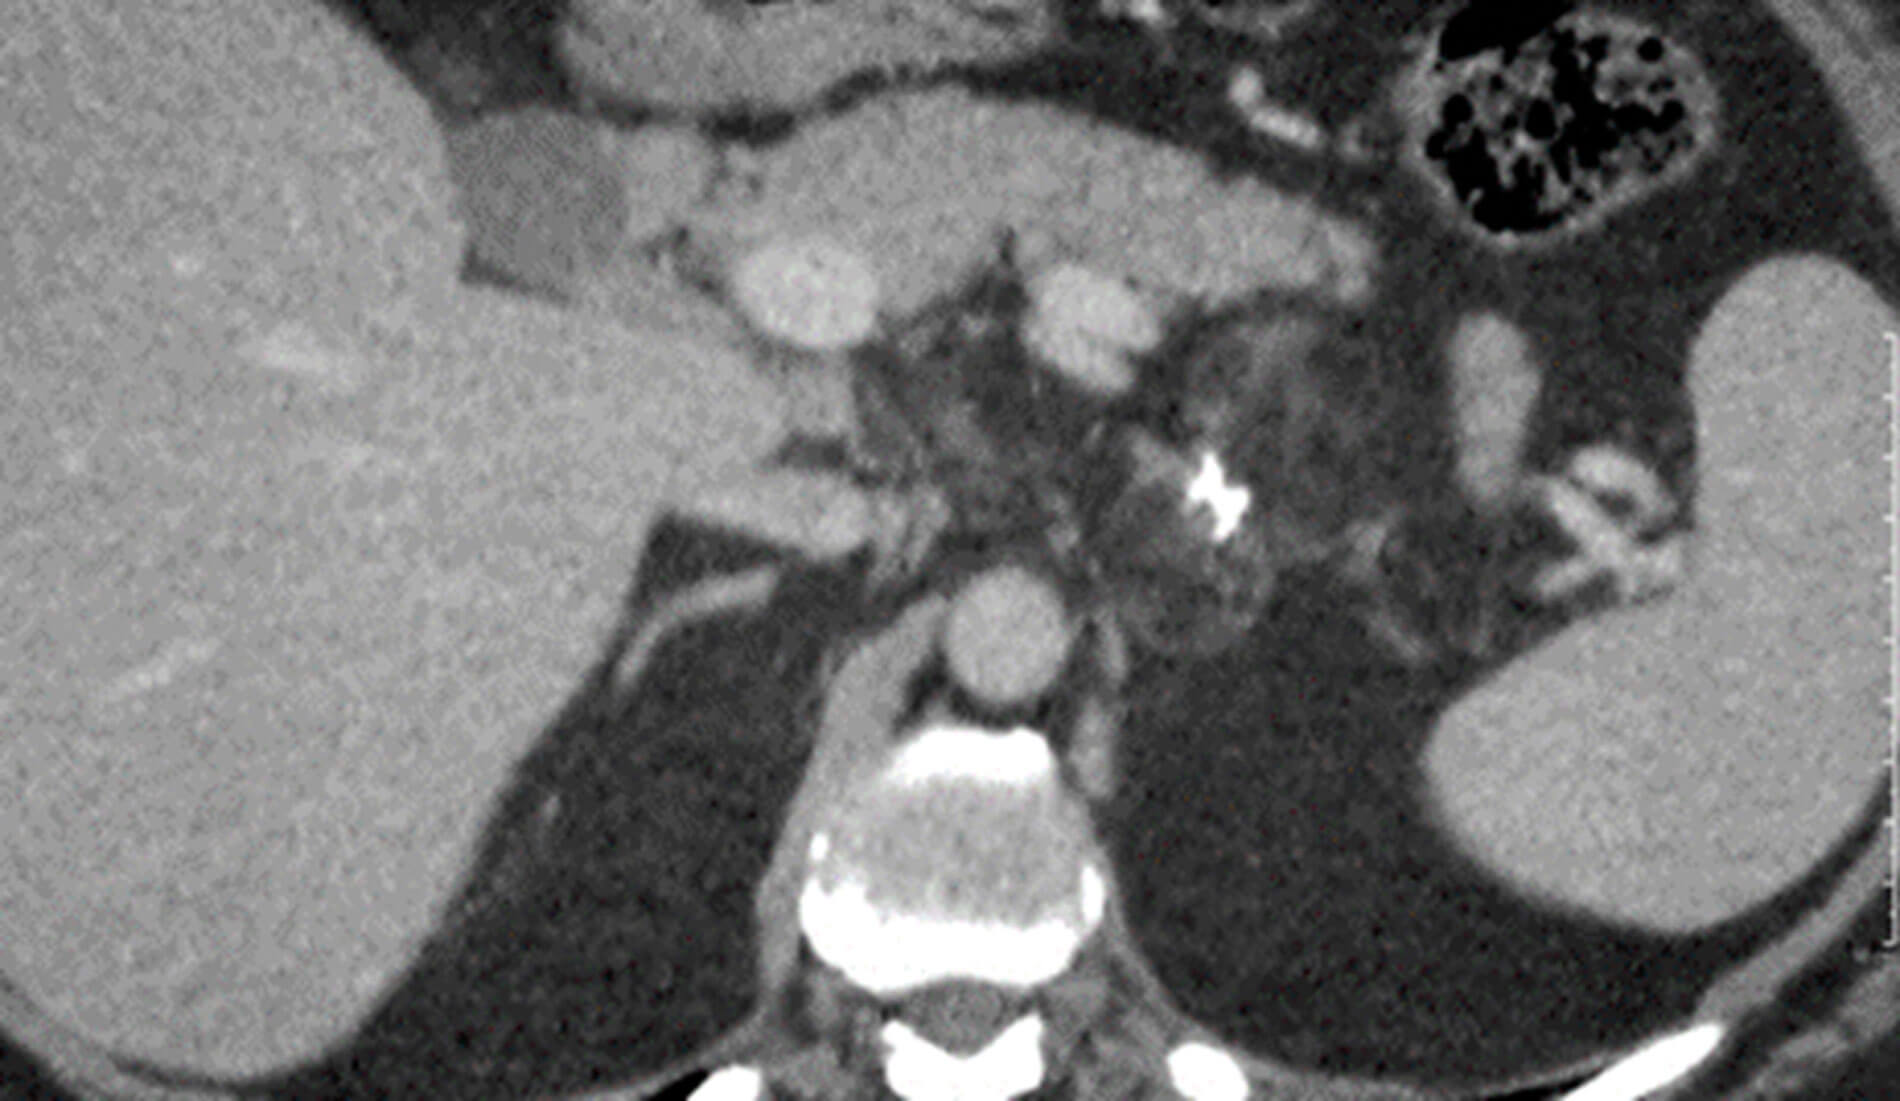

Figure 1: Axial portal venous CT image shows a 5.5 cm bilobed low attenuation mass arising from the left adrenal gland. There are foci of coarse calcification centrally and a large macroscopic fat content consistent with a benign myelolipoma.